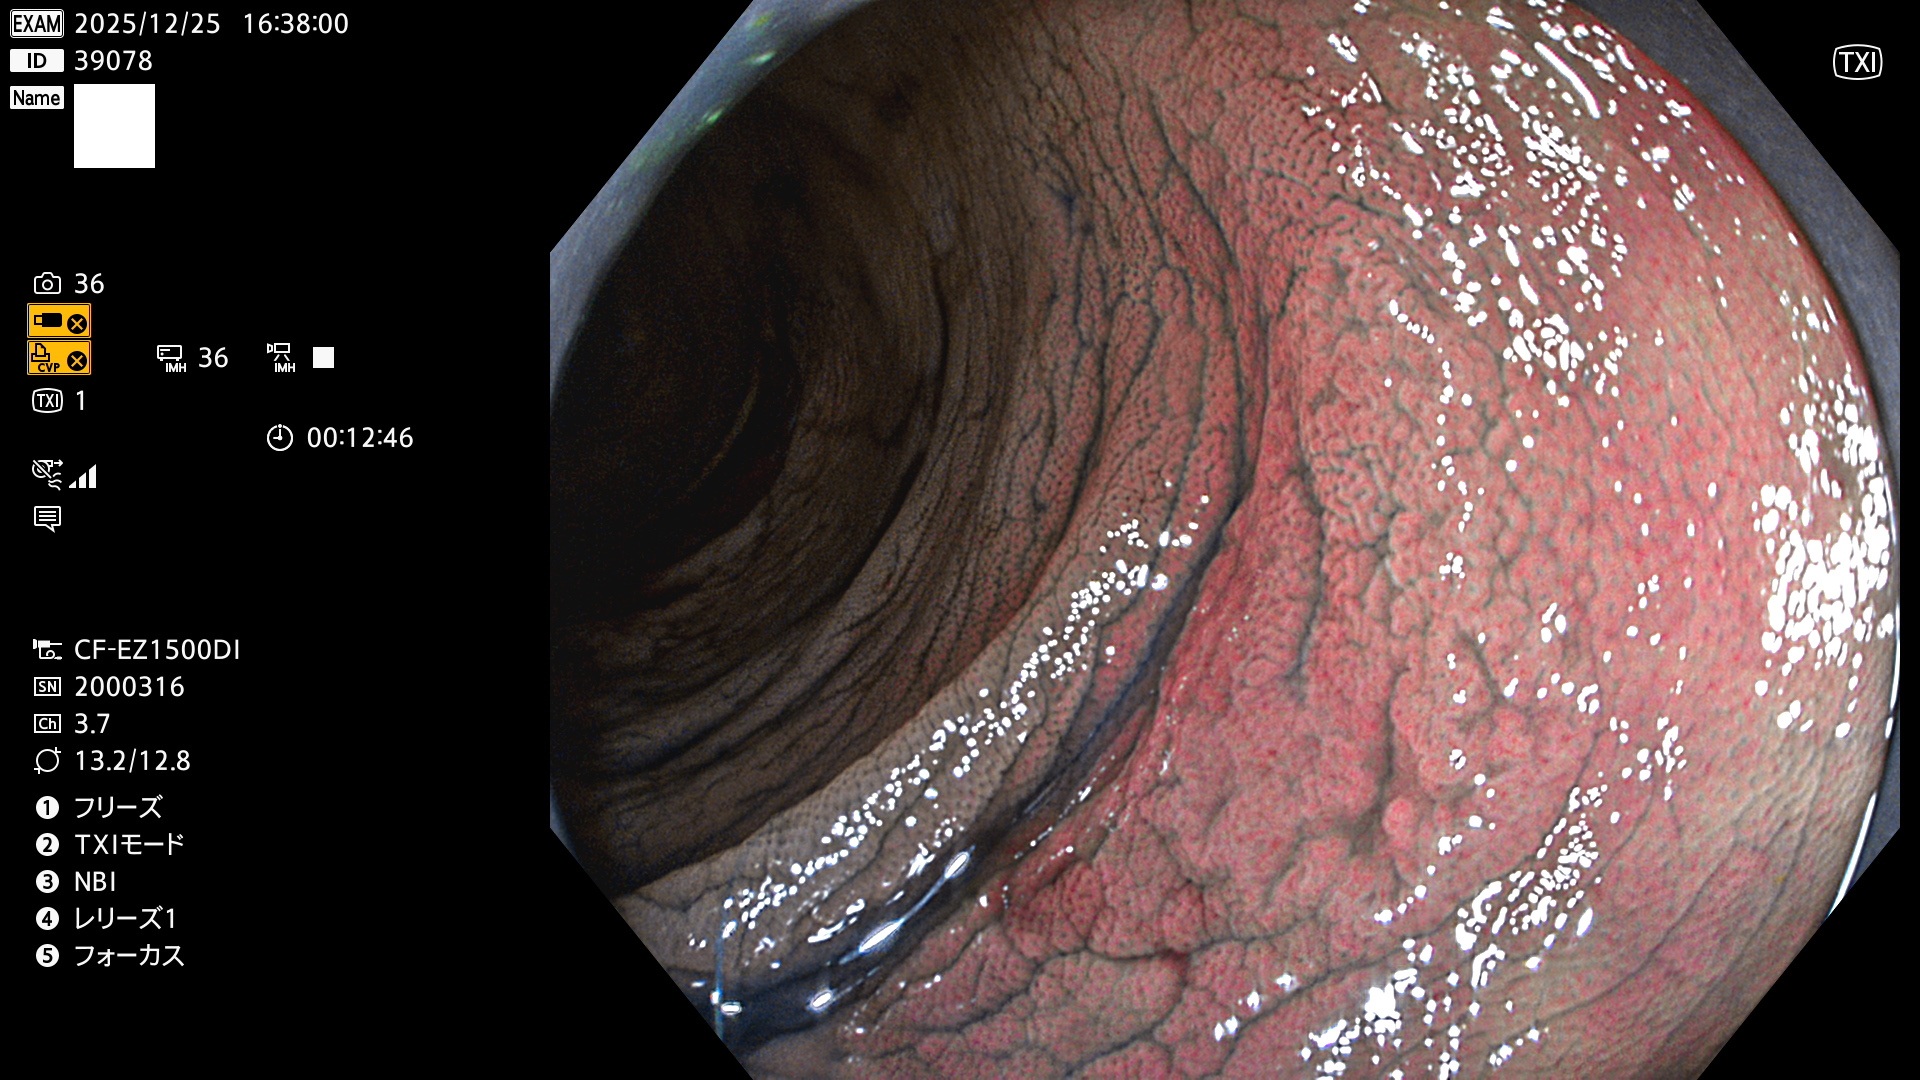

完全に平坦な物をUb、陥凹している物をUcと呼びます。Ubは認識が困難で、Ucはびらん(炎症)と紛らわしいために見落とされやすく、「内視鏡後・大腸癌」の原因になります。

毎週の検査(木・金・土・日)に発見されたUbとUc型・腺腫を、その週の日曜の夜にUPし1週間、提示します。

2025年12月18日〜12月29日の8日間(80件)13個 (Uc_ADR=13個/80人=16%)